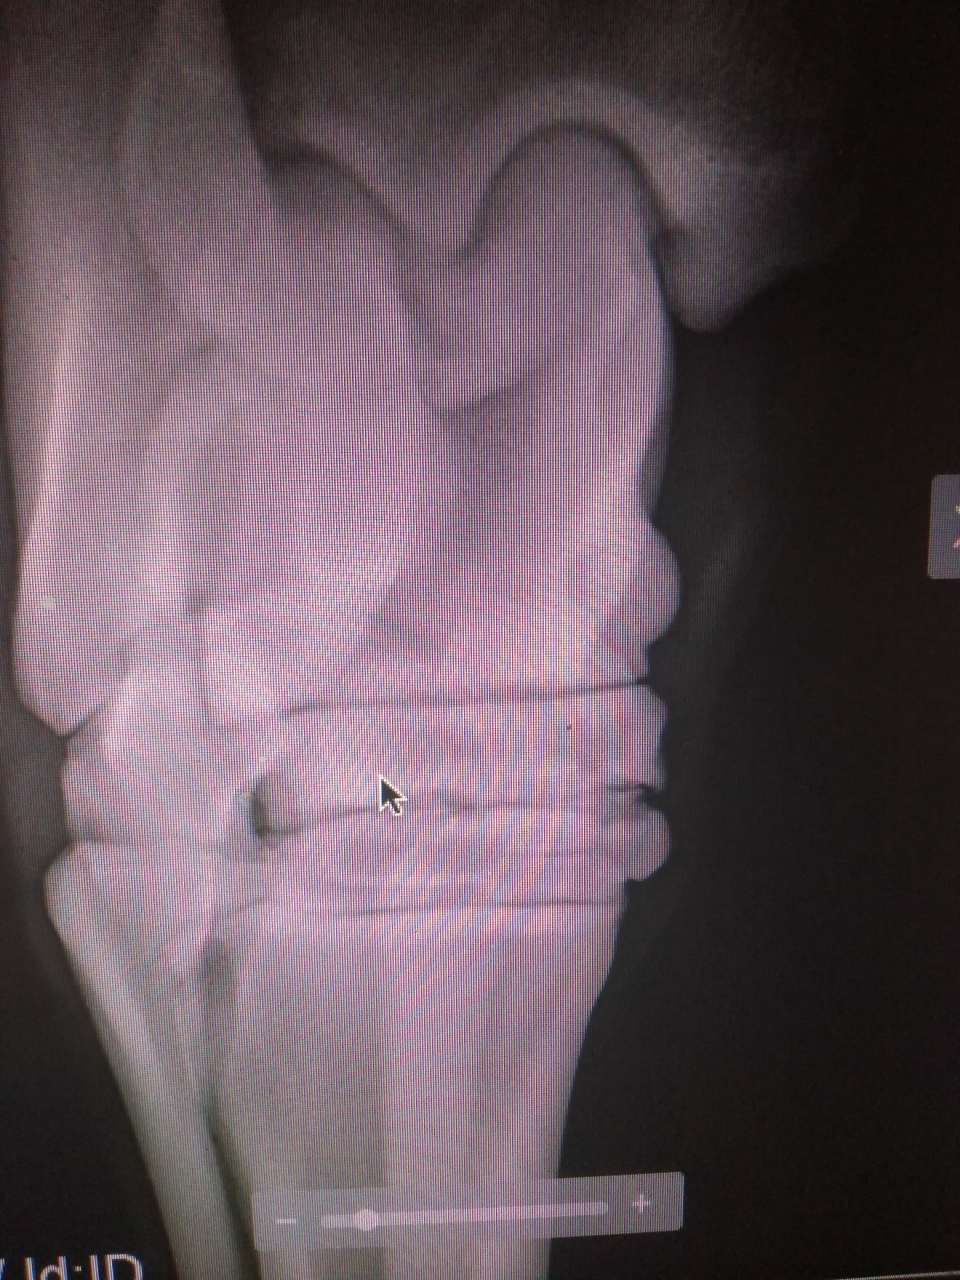

| Dire merci | peuton voir ces fameuses RX ? |

Par sarah69 : le 03/08/19 à 22:10:53

DéconnectéDire merci | v![]() ![]() |

Par sarah69 : le 03/08/19 à 22:11:46

DéconnectéDire merci | desolee por les images mais je ne voulais pas poster en ligne le nom du cheval |

| Dire merci | Mais ce n’est pas d’un antérieur qu’il boite ce cheval? Après en effet s’il a écrit RAS sur les jarrets à la lecture des clichés (bien que vu la qualité on induit plus qu’autre chose) mais de là a parlé d arthrose non par contre d’autres choses pourquoi pas . Message édité le 03/08/19 à 22:49 |

DéconnectéDire merci | excuse moi lapateuh, je n ai pas compris ce que tu veux dire j ai pris une photo des radios...desolee pour la qualité Message édité le 03/08/19 à 22:50 |

| Dire merci | Faire un DG sur deux clichés (en imaginant que ce soit le même membre) c’est quand même un peu légère surtout vu l’image actuellement mise sur le forum. Surtout sans image comparative de l’autre membre. Et je ne comprends pas l’histoire du jarret avec la boiterie d’un antérieur. |

DéconnectéDire merci | l histoire en bref c est que quand le cheval est arrive, je l ai fait parer et il a montre une forte sensibilité et boiterie d un antérieur qui s est bien estompée au bout de quelque jour, du coup, j ai envoye les rx a un veto avec lequel je travail qui m a indique la présence d arthrose au niveau du jarret droit. Le veto de la visite d achat (qui est a 800 km) me dit que non...les radios sont les deux du meme jarret |